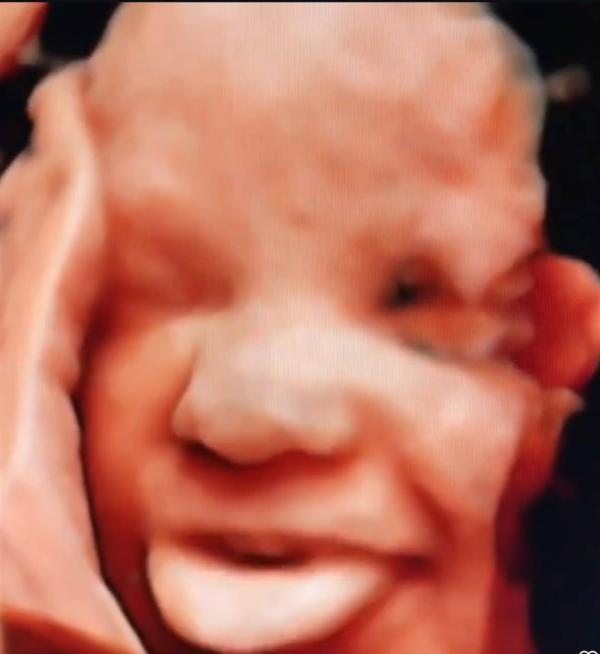

Я работаю на узи с 2007 г, т.е. уже 18 лет. 3д делаю с 2015 г, т.е. 10 лет.

Сейчас покажу фотки с 2015 ,2016 ,2018 гг.

И они нисколечко не уступают по красоте и качеству сделанным сегодня или вчера .

Если не нравится, проходите мимо. Мне очень нравится, поэтому делюсь . Это самое милое и очаровательное, что есть в этом мире . 😍